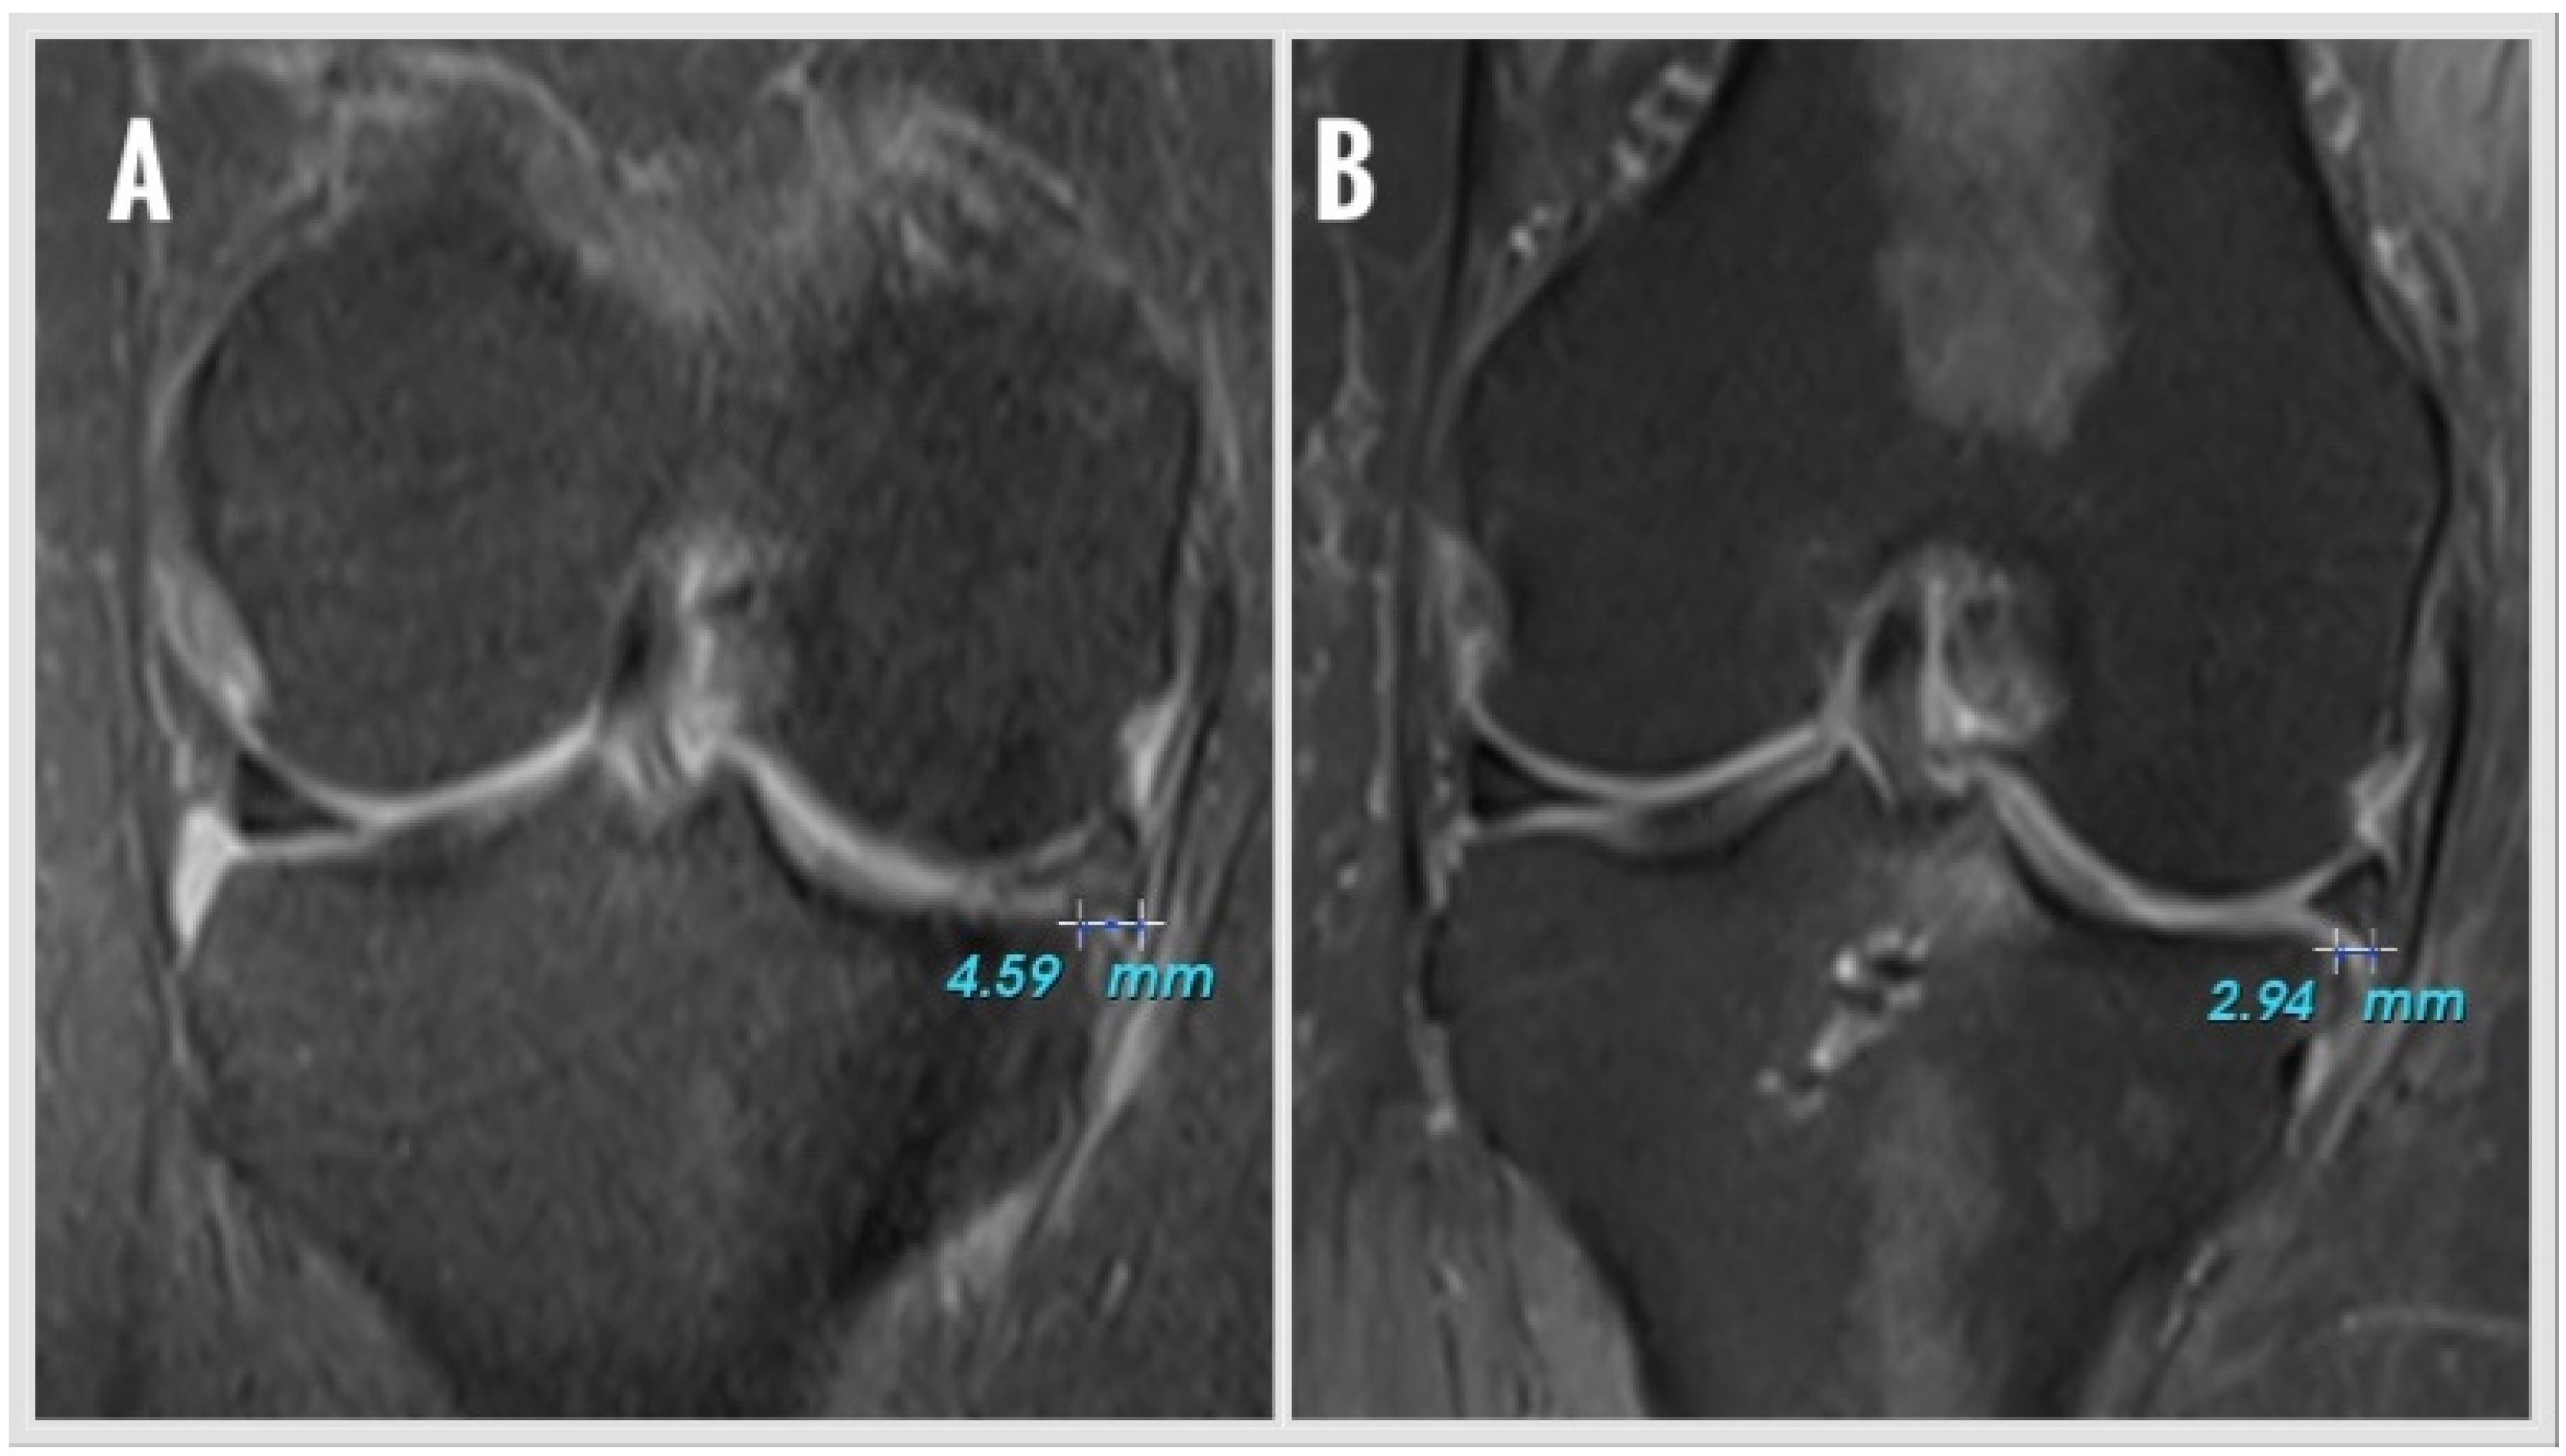

Figure 1. Meniscus extrusion (ME) measurement on coronal MRI section showing the most prominent appearance of the tibial eminence. (A) preoperative ME value, (B) postoperative ME value.

ME was measured on coronal MRI showing the most prominent appearance of the tibial eminence (Figure 1). A vertical line was drawn from the outer border of the medial tibial plateau, and extrusion was defined as the distance (millimeters) between this line and the outer edge of the medial meniscus. Osteophytes, if present, were excluded from the determination of the tibial plateau margin. The same two blinded observers (Y.M.A., Ö.C.Ç.) performed all the radiologic measurements. Measurements were evaluated intra-inter observer. All intraclass correlation coefficients (ICCs) were above 0.80. The mean of four measurements was used for statistical analysis.

The mean medial ME decreased from 5.0 ± 2.1 mm (range: 2.7–9.0 mm) preoperatively to 4.6 ± 2.1 mm (range: 2.0–9.2 mm) postoperatively. This reduction in extrusion was not statistically significant (p = 0.178). At the final follow-up, all patients demonstrated full range of motion in the operated knee.